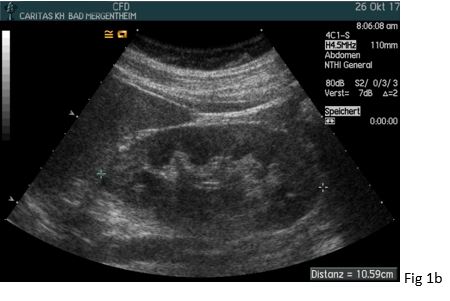

A 37 yo female patient suffered from chronic headaches. She was examined by a neurologist who diagnosed fibromyalgia. Her family practioner also diagnosed severe arterial hypertension (so-called “non dipper”) and excluded hyperaldosteronism, hyperthyroidism and sleep apnoea as secondary causes. Anti-hypertensive medication was initiated with amlodipine and ramipril. Although she is a smoker (> 20 py) there were no ultrasonic features of atherosclerosis. However, her estimated glomerular filtration rate was reduced (~68 ml/min/1,73m²). Auscultation also revealed a high frequent upper quadrant noise on the right side. The general practioners initial ultrasound showed a significant difference in the size and resistive index (RI) between the right and left kidney. For that reason, the patient was sent to our specialist hypertension center where the diagnosis of renal artery stenosis caused by fibromuscular dysplasia was confirmed.

The peak systolic velocity (PSV) in the renal artery is physiologically below < 1.5 m/s and typically around 1 m/s. In contrast, values > 1.8 m/s are indicative of significant stenosis. The normal RI values within the kidney are in the range of 0.55 - 0.65 and typically below 0.7. The normal values are increasing with age (up to 20 %) (1, 5, 6).